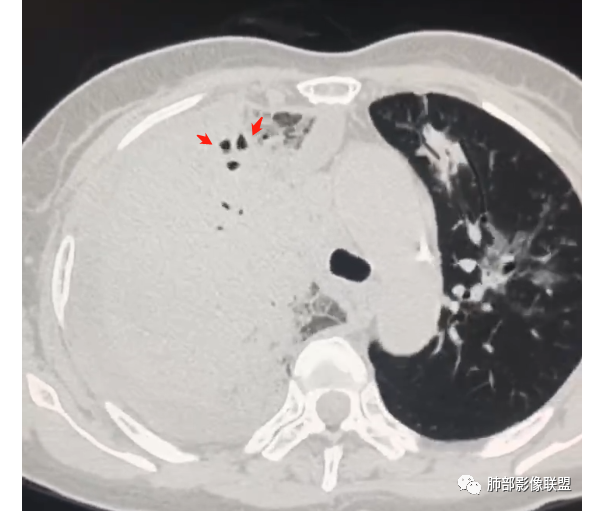

第一次CT:

首先考虑感染性病变,合并右侧胸腔积液,增强扫描强化明显,左侧也有少许感染,病变无坏死,可见支气管充气征,支气管镜上叶管腔狭窄,未见新生物。

右肺大叶实变,支气管扩张,有强化,胸腔积液考虑淋巴瘤 ,鉴别奴z卡,结核感染。

急性起病与影像表现不符,右肺大片状实变,内见支气管通气象,部分支气管不规则扭曲。左肺磨玻璃病变增多。考虑腺癌可能。

右肺肿块,极度不规则,内部有空气支气管,增强扫描中度不均匀强化。左肺有多发片状实变,边界清,内部有支气管穿行。左侧大亮胸腔积液。胸闷,咳白痰。支持恶性肿瘤,腺癌可能

女,65,胸闷、气短6天。胸部CT:左肺多发斑片实变影/GGO,边缘模糊,隐约有小叶内间隔增厚,沿支气管束分布。右上叶大叶性实变影,支气管充气征,部分管腔扩张;右中下叶大片实变影,沿支气管分布,边缘清晰、内收明显。右侧胸腔积液,纵隔可见肿大淋巴结。考虑:TB?PC?鉴别粘液腺癌。

中老年女性,急性病史,全身症状,提示全身多部位受累。5,29:右肺大量胸水压迫,导致肺叶不张夹杂其中,无法观察病灶实质;左肺病灶沿支气管血管束走向,无叶段性分布,提示间质为主病变。